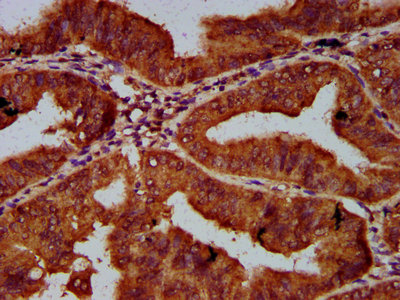

IHC image of CSB-PA617942LA01HU diluted at 1:600 and staining in paraffin-embedded human endometrial cancer performed on a Leica BondTM system. After dewaxing and hydration, antigen retrieval was mediated by high pressure in a citrate buffer (pH 6.0). Section was blocked with 10% normal goat serum 30min at RT. Then primary antibody (1% BSA) was incubated at 4°C overnight. The primary is detected by a biotinylated secondary antibody and visualized using an HRP conjugated SP system.